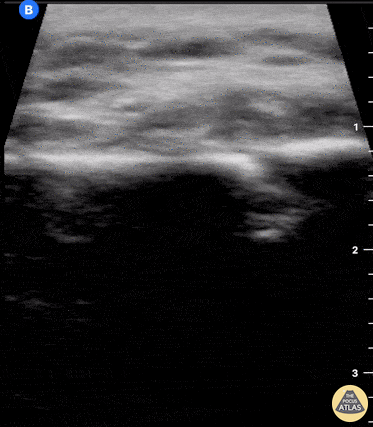

Musculoskeletal - Clavicle fracture with hematoma

60 year old female with a subacute left clavicular fracture (occurred 2 weeks ago) presented with worsening pain at fracture site of onset while working with occupational therapy. Seen here is the left clavicle (hyperechoic structure) with noted fracture and mild heterogeneous (concern for bloody accumulation) edema around fracture site as observed in long axis view. Kwasi Ampomah, DO, Eben Alexander IV, DO, Tariq Niazi, MD EVMS PM&R